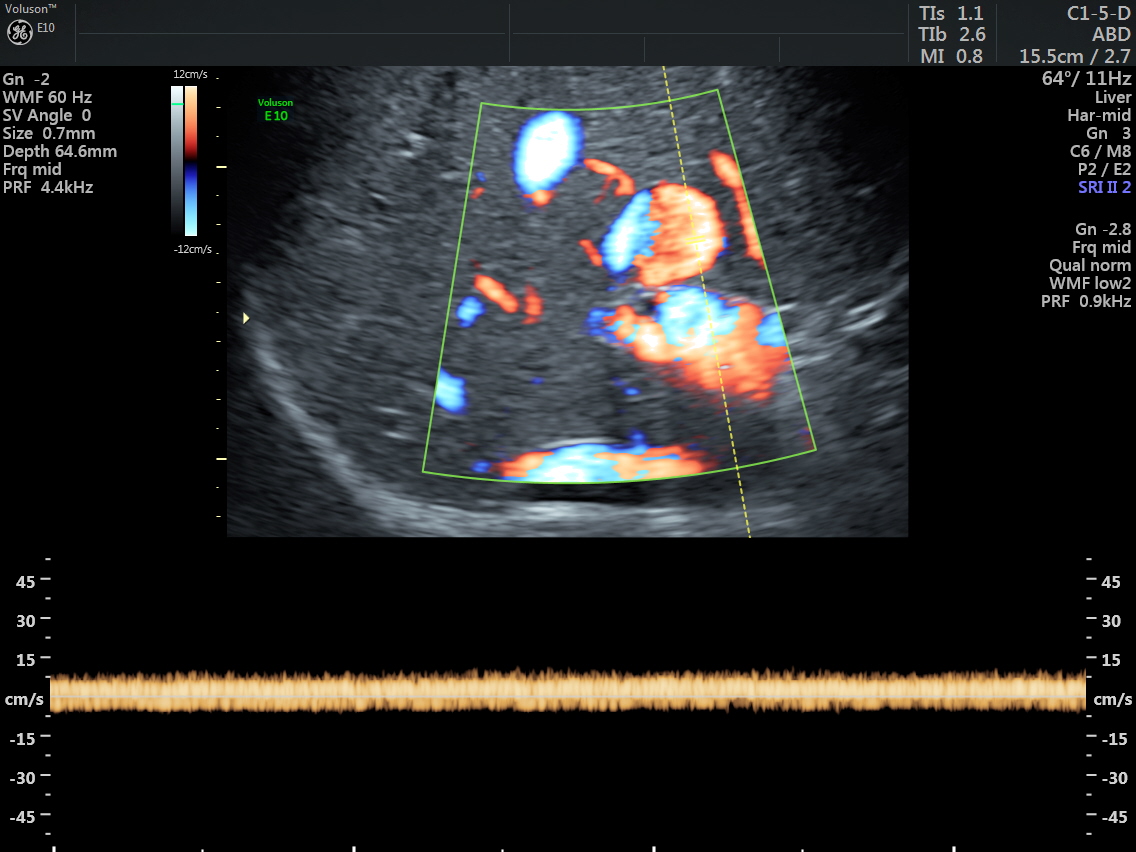

The venous flow is established by power doppler in the following pictures.

Reconstructed images show the feeding vessel and a vessel leaving the vascular structure.